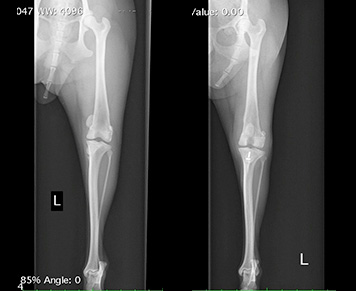

画像診断

レントゲン検査では膝蓋骨の位置だけでなく関節炎の有無の確認、関節液の貯留や脛骨前方変位などの前十字靭帯損傷の兆候がないか膝関節の異常の評価や大腿骨の変形、脛骨粗面の変形の確認をします。

手術を行う場合にはレントゲン画像を見ながら手術の術前計画を考えます。

グレードの高い症例やレントゲン検査で大腿骨の変形が疑われる症例ではCT検査で大腿骨の変形、股関節の異常の確認をする場合があります。 -

症例:トイプードル 年齢:1歳5か月 体重:2.3kg

たまに左後肢を挙上し、スキップのような歩行をするのが気になるという主訴で来院されました。

触診で右膝蓋骨内方脱臼グレード1、左膝蓋骨脱臼グレード3と診断。 レントゲン検査でも膝蓋骨内方脱臼を確認できました。関節液も軽度に貯留が認められました。左膝関節は若齢でありながら重度の膝蓋骨脱臼に罹患しており手術による整復術を提案、実施しました。右膝関節は症状もなくグレードも低いため経過観察となりました。